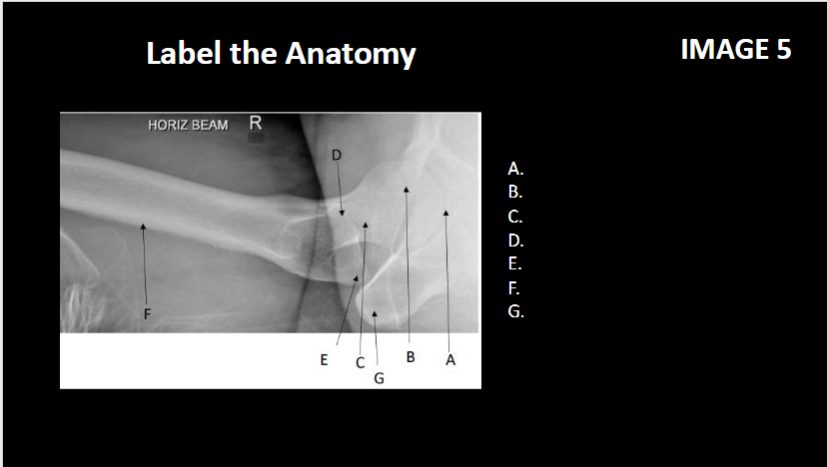

A

Femoral neck

B

Left Greater trochanter

C

Left lesser trochanter

D

Iscial tuberosuty

E

Left femoral heas

f

Abetalubum

Projection?

Ap oblique modified cleaves

Identify projection

Ap hip

this position is used to observe what anatomy

Greater trochanter in profile laterally, femoral neck wo foreshortening

Projection

Ap axiolatetal

what is the patient position

supine, unaffected limb raised